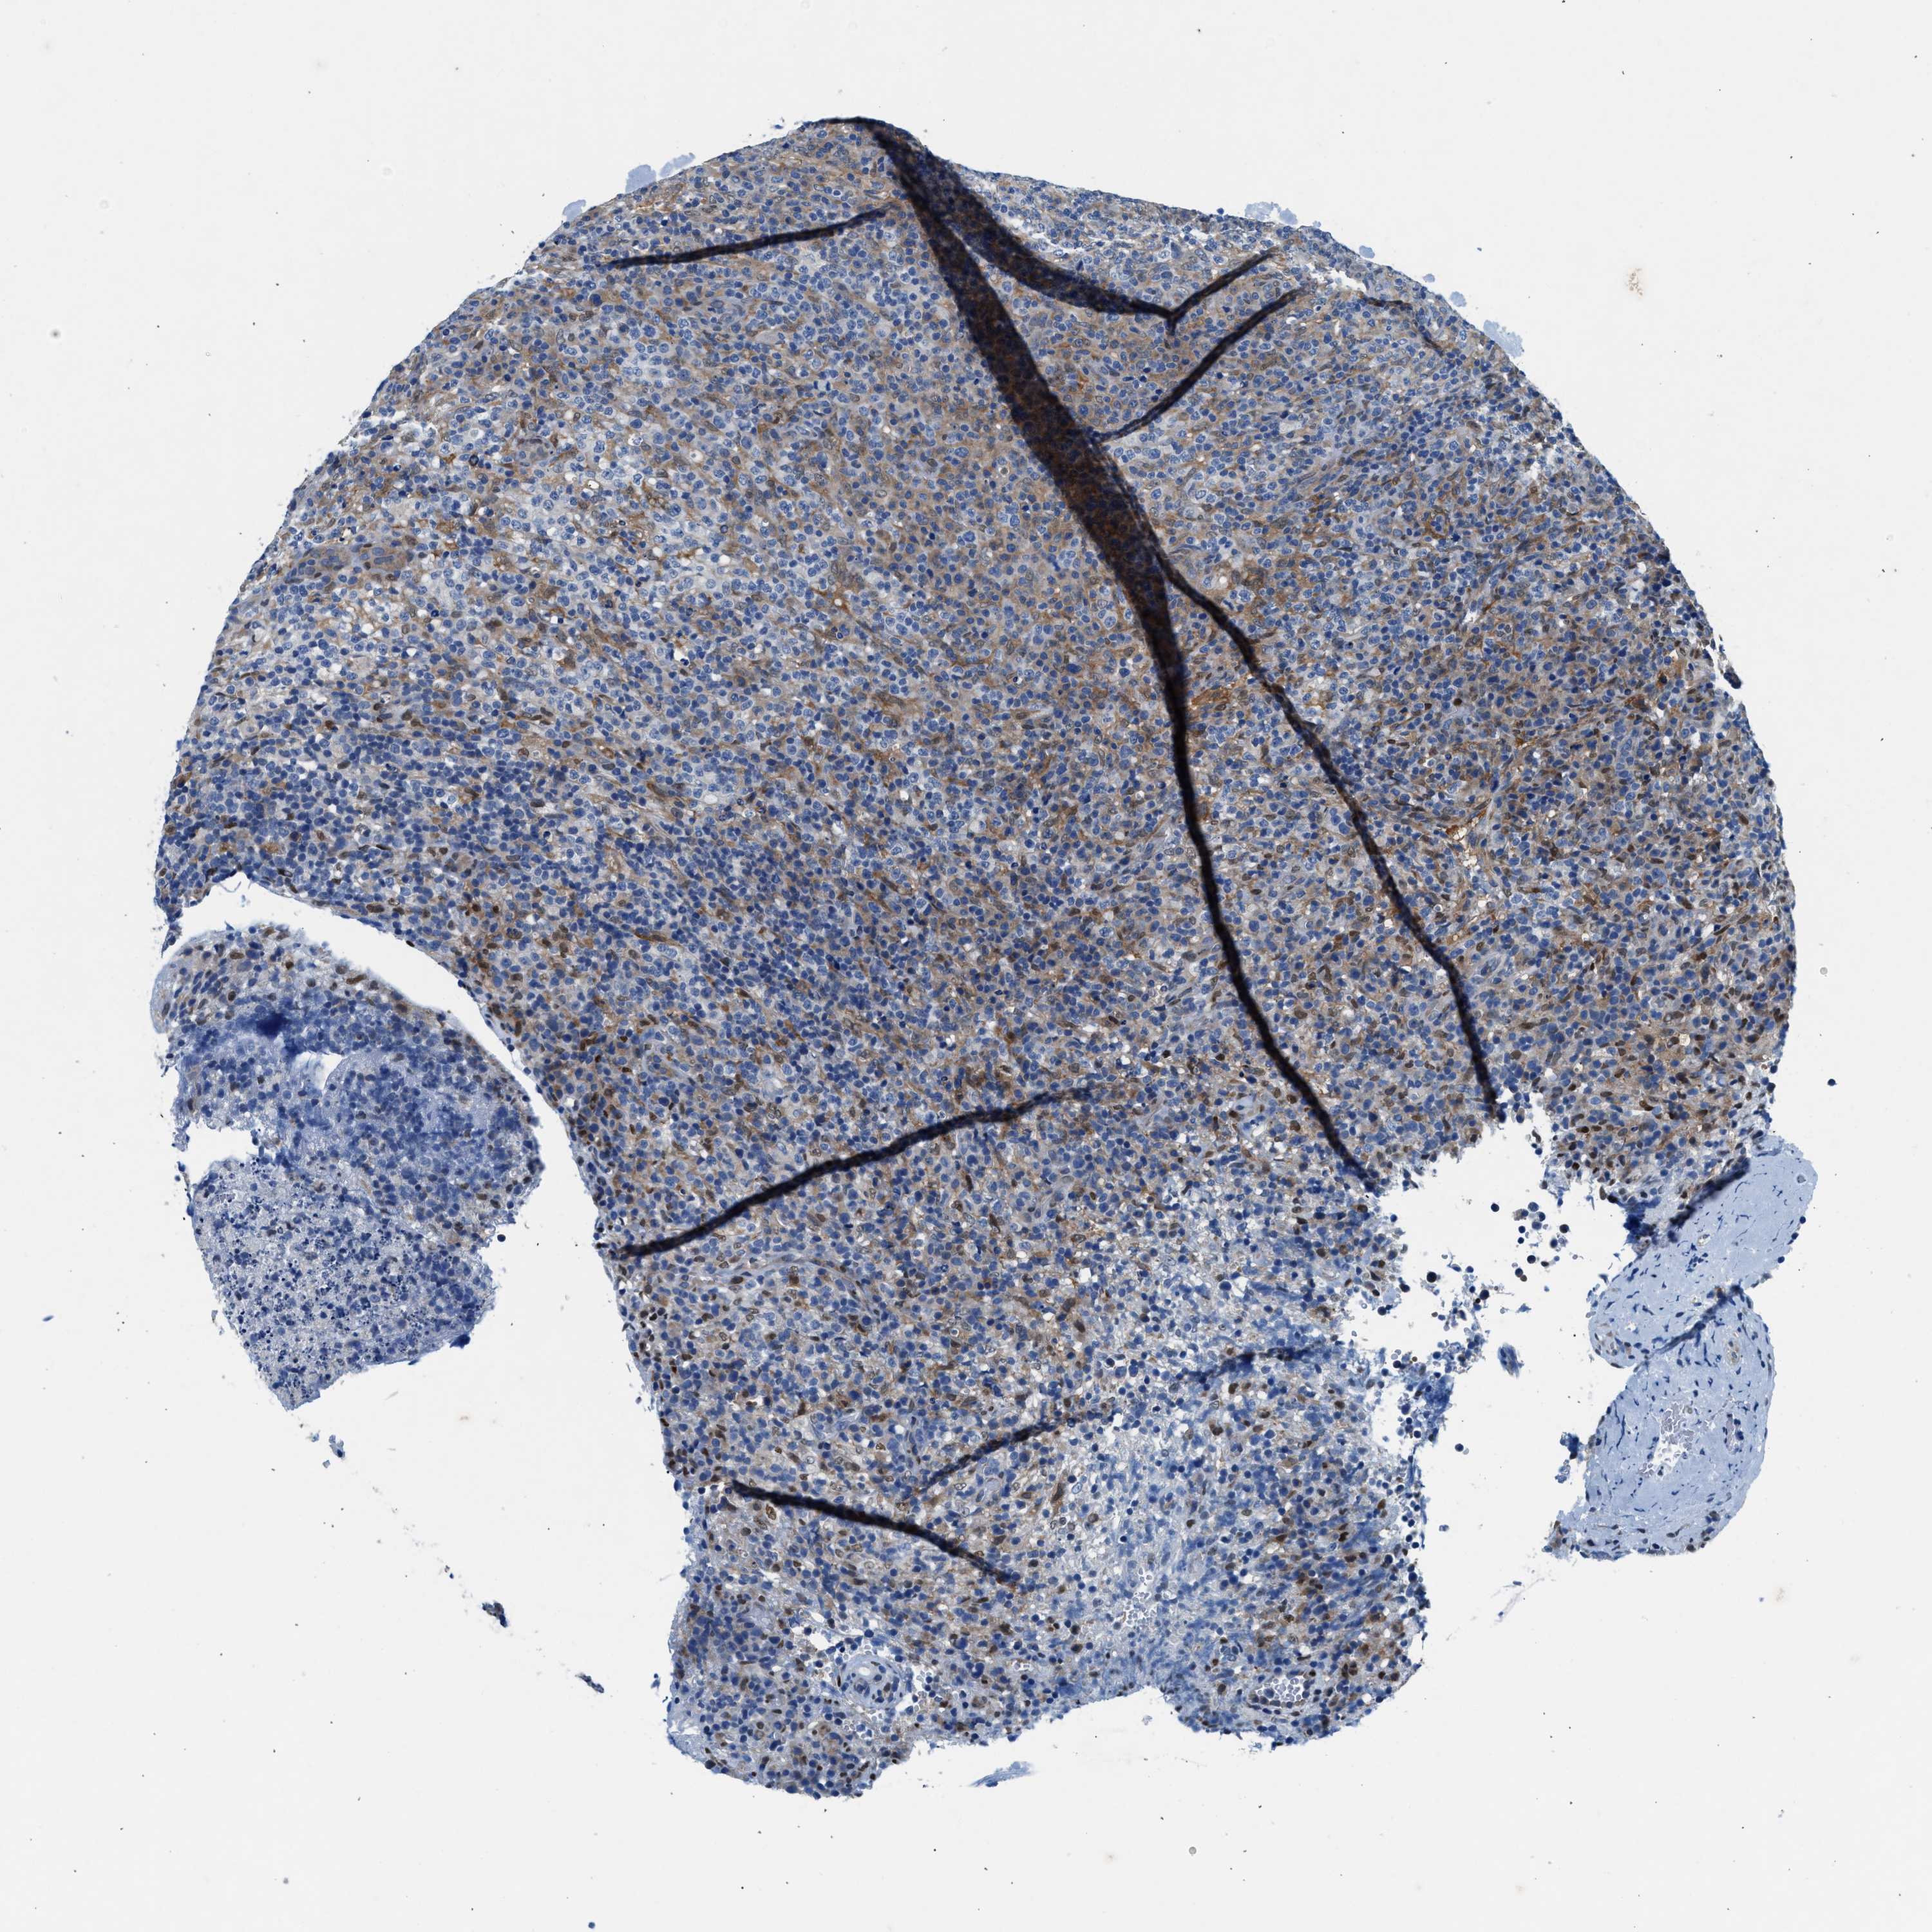

CANCER LYMPHOMA Show tissue menu

LYMPHOMA - Protein expressioni

A mouse-over function shows sample information and annotation data. Click on an image to view it in a full screen mode. Samples can be filtered based on level of antibody staining by selecting one or several of the following categories: high, medium, low and not detected. The assay and annotation is described here.

Antibody stainingi

Antibody staining in the annotated cell types in the current human tissue is reported as not detected, low, medium, or high, based on conventional immunohistochemistry profiling in selected tissues. This score is based on the combination of the staining intensity and fraction of stained cells.

Each image is clickable and will lead to virtual microscopy that enables deeper exploration of all samples and also displays staining intensity scores, fraction scores and subcellular localization as well as patient and tissue information for each sample.

Antibody HPA016867

Antibody HPA018271

Hodgkin's disease, NOS

Malignant lymphoma, non-Hodgkin's type, High grade

Malignant lymphoma, non-Hodgkin's type, Low grade